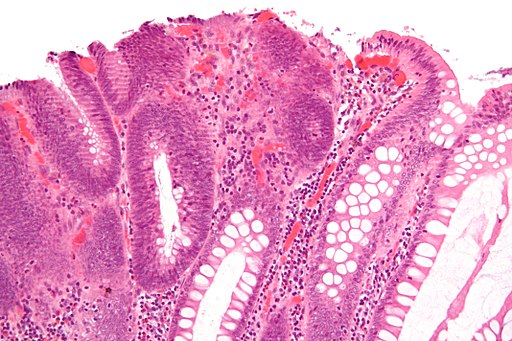

Dysplazie jsou morfologické změny jednotlivých buněk a jejich uspořádání ve tkáni, typ tkáně se však celkově nemění. Vzniká vlivem chronického dráždění (např. virová infekce, kouření, mechanické dráždění), při trvajícím dráždění se změny…

Dysplazie je termín užívaný v patologii odkazující na poruchu vývoje nebo růstu. Při této poruše vývoje často dochází k expanzi nezralých buněk (jako například buňky ektodermu) s odpovídajícím úbytkem zralých buněk. Dysplazie často svědčí pro počínající neoplastický proces. Termín dysplazie je často používán v případě, že buněčná odchylka je limitována na výchozí tkáň, jako v případě in-situ neoplastických procesů. Způsobuje vyšší riziko vzniku zhoubného nádoru. Na jejím vzniku se podílí… Wikipedie